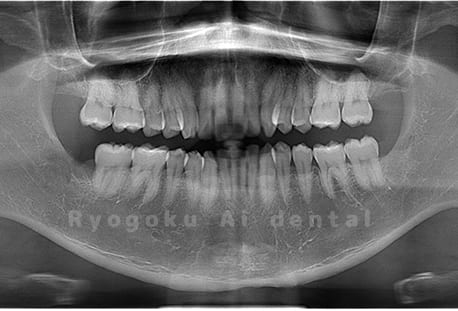

Case05

- 原因

- 下顎の親知らず2本

- 治療内容

- 下顎の親知らず2本を抜歯したケースです。

<リスク・副作用>

手術後は痛み、腫れ、痺れなどの副作用が生じる場合があります。